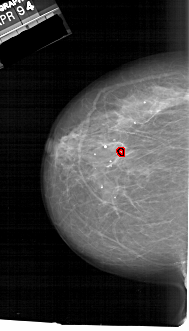

A_1728_1.LEFT_MLO

LEFT_MLO LINES 6511 PIXELS_PER_LINE 3871 BITS_PER_PIXEL 12 RESOLUTION 43.5 OVERLAY

FILE: A_1728_1.LEFT_MLO.OVERLAY

TOTAL_ABNORMALITIES 1

ABNORMALITY 1

LESION_TYPE CALCIFICATION TYPE PLEOMORPHIC DISTRIBUTION CLUSTERED

ASSESSMENT 4

SUBTLETY 2

PATHOLOGY MALIGNANT

TOTAL_OUTLINES 1

BOUNDARY